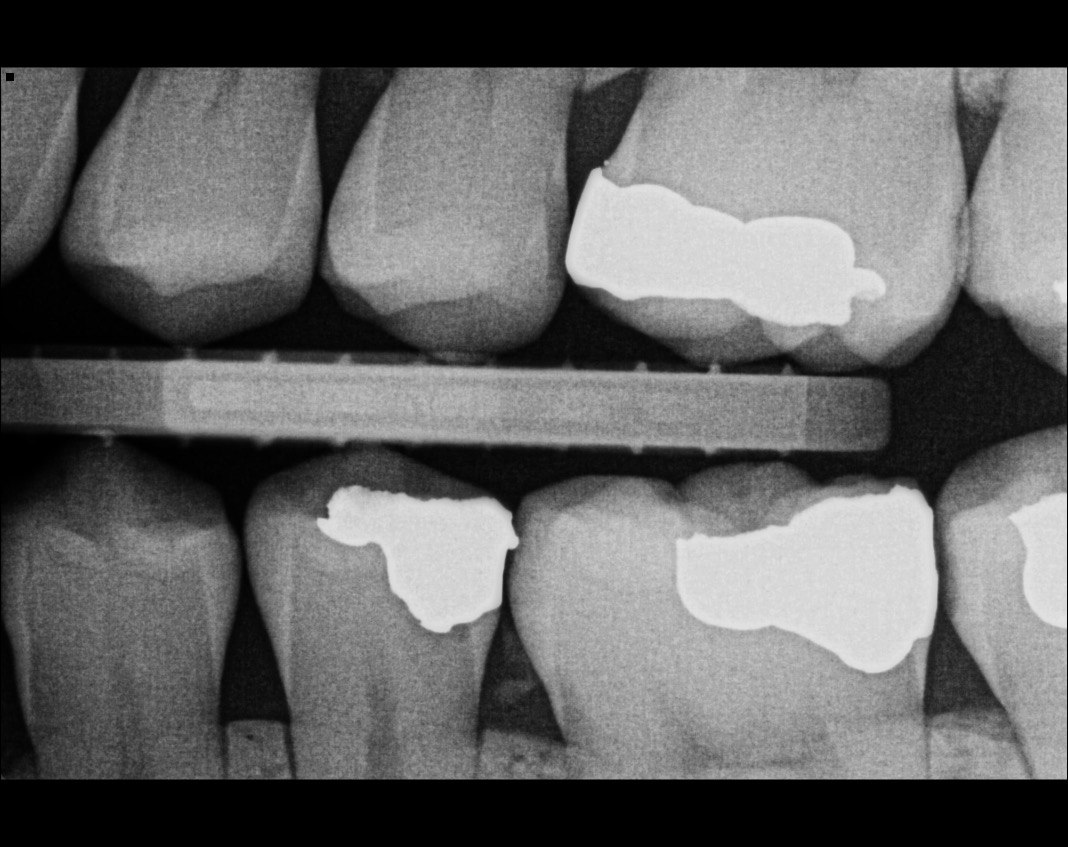

Quistion 11: What are the conditions of the distal and mesial surfaces of the tooth # 4.5 respectively?

Question 12: What option can describe the mesial surface of the tooth # 3.7?

Question 13: What option can describe the mesial surface of the tooth # 3.8?

Question 14: What option can describe the mesial surface of the tooth # 3.4?

Question 15: What option can be selected for treatment of the caries in mesial surface of the tooth # 3.4?

Question 16: What option can be chosen for the treatment of the mesial surface of the tooth # 3.7?